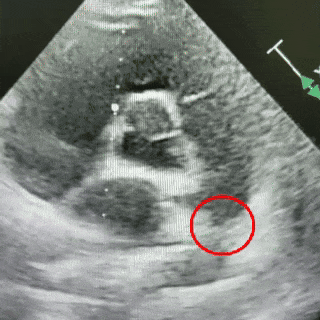

术后6个月随访

无残余分流,封堵效果良好